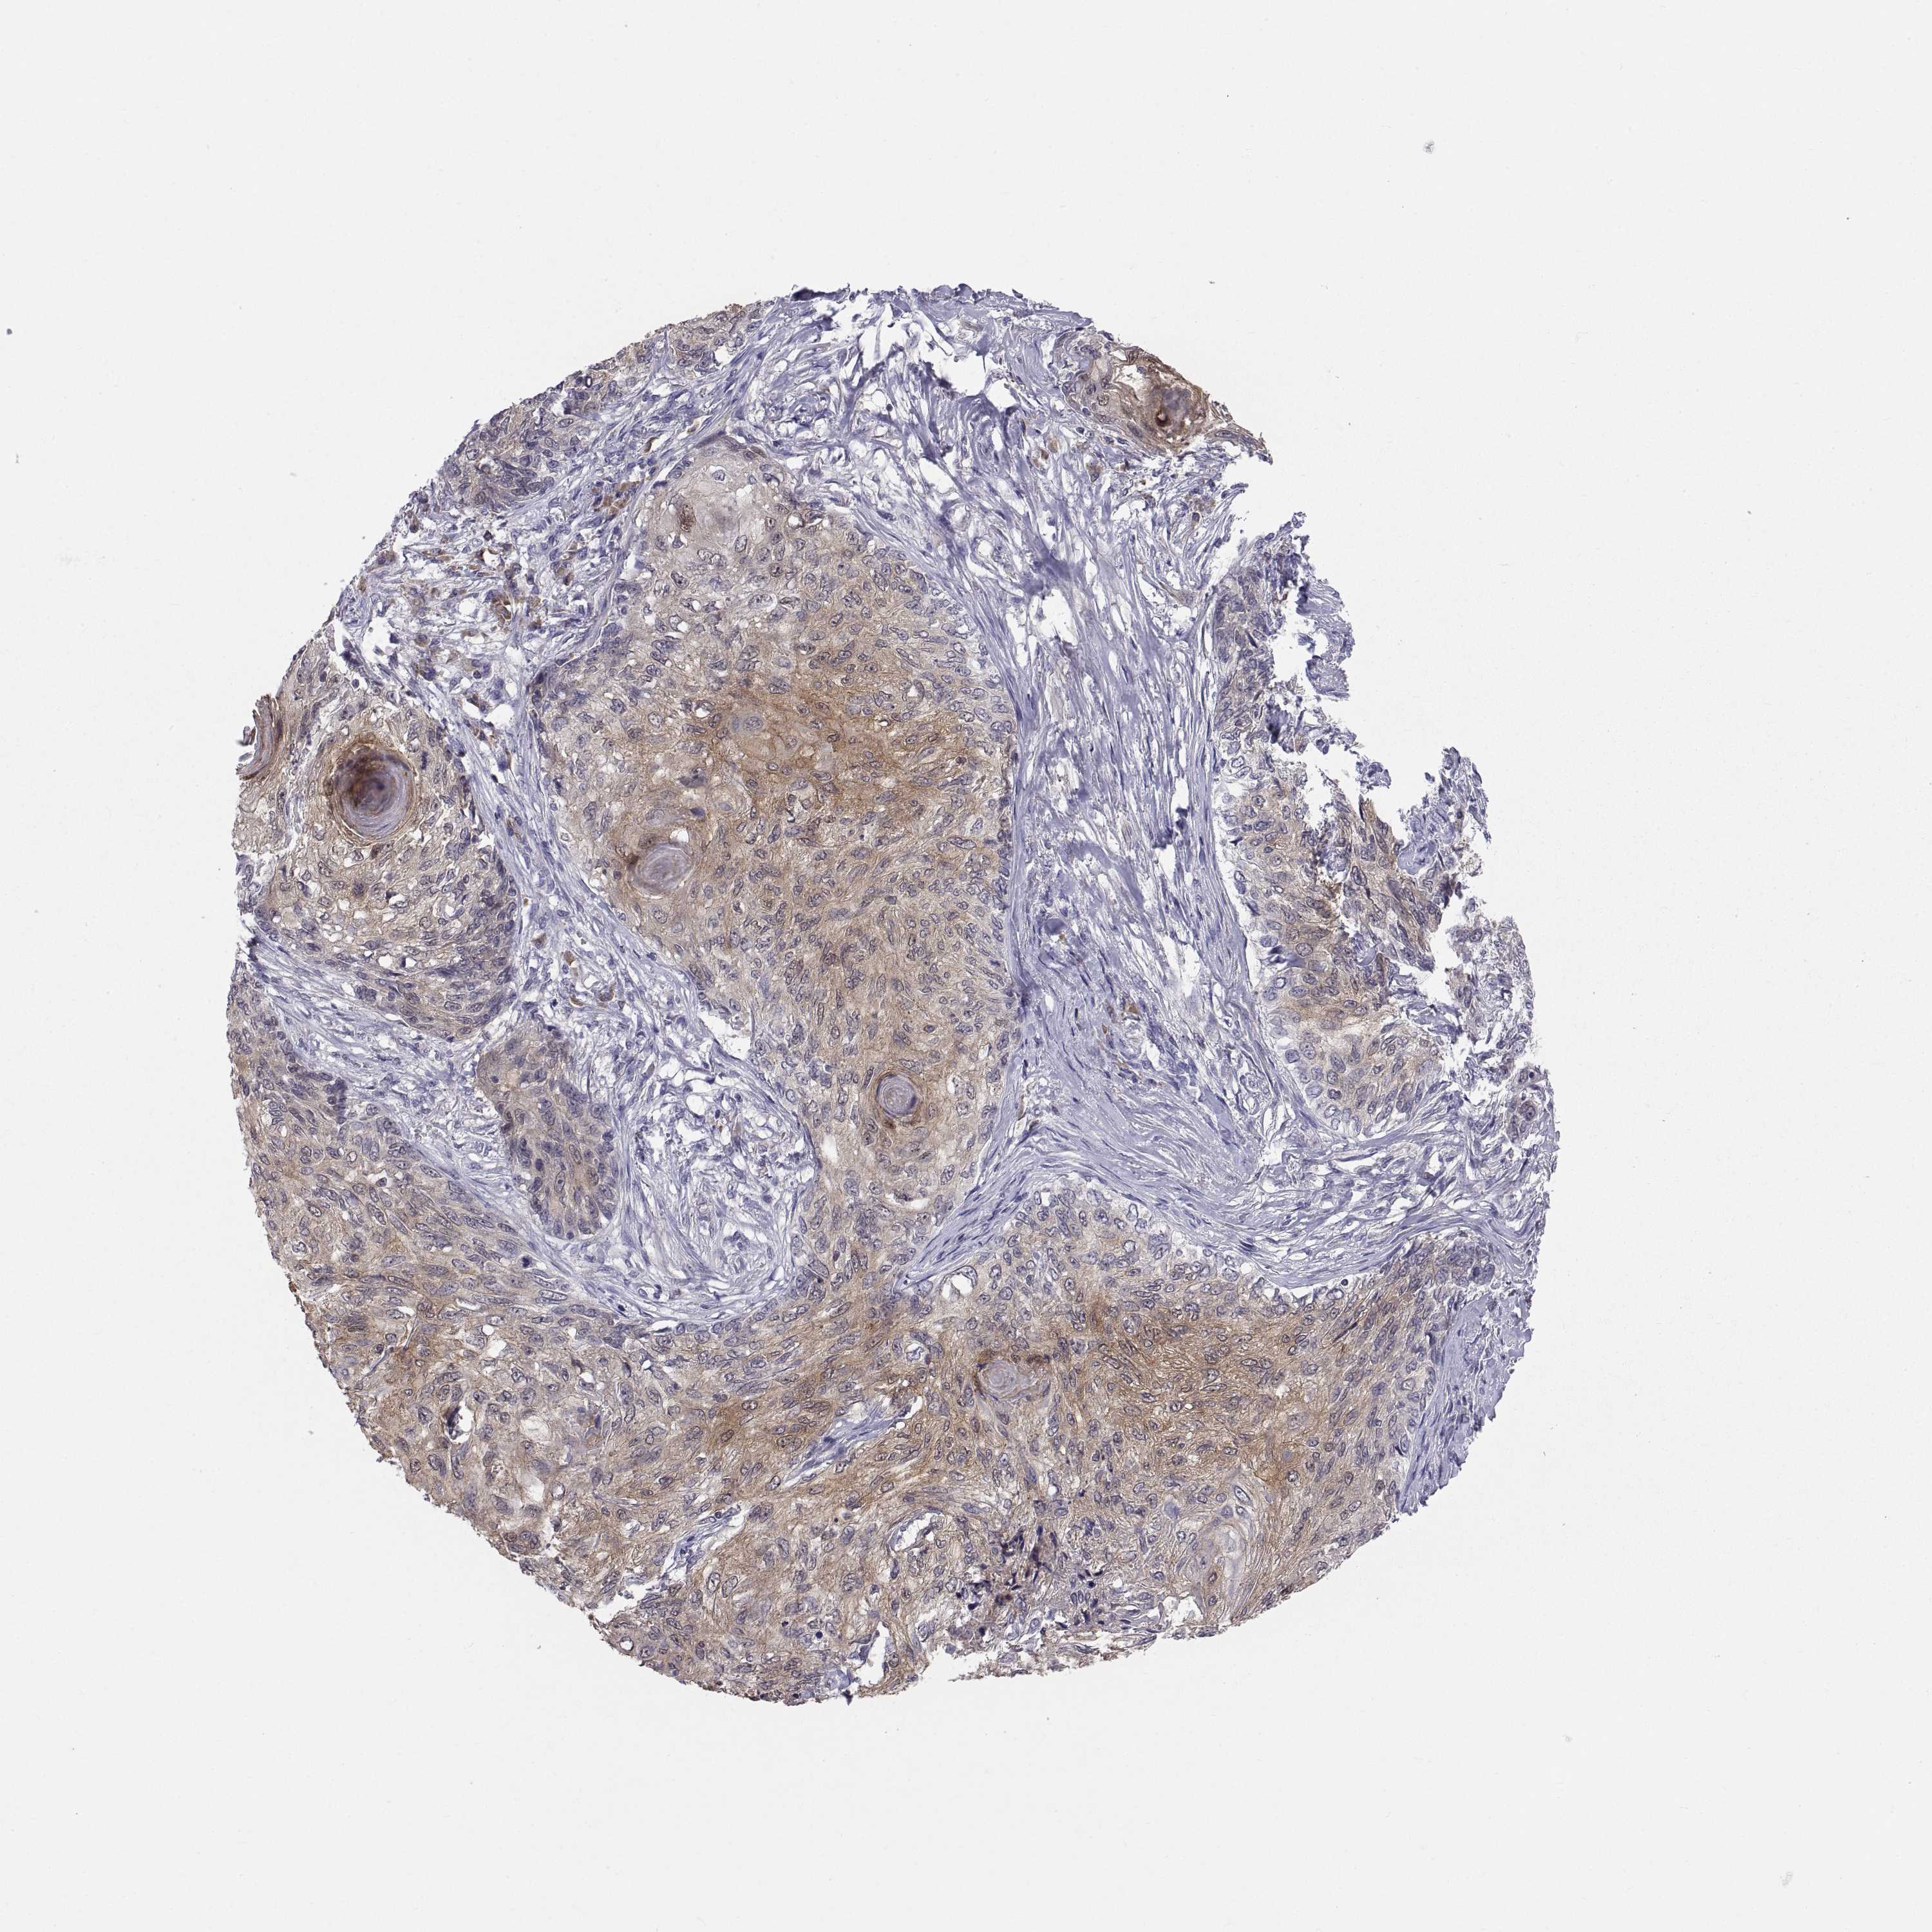

SKIN CANCER - Protein expressioni

A mouse-over function shows sample information and annotation data. Click on an image to view it in a full screen mode. Samples can be filtered based on level of antibody staining by selecting one or several of the following categories: high, medium, low and not detected. The assay and annotation is described here.

Each image is clickable and will lead to virtual microscopy that enables deeper exploration of all samples and also displays staining intensity scores, fraction scores and subcellular localization as well as patient and tissue information for each sample.

Antibody HPA027221

Basal cell carcinoma

Squamous cell carcinoma, NOS